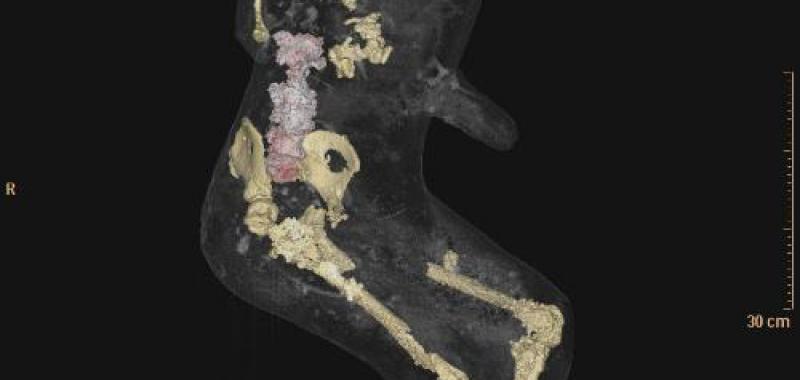

Por primera vez, un grupo de moldes de yeso de Pompeya ha sido sometido a tomografías axiales computerizadas (TAC), a partir de las que ha sido posible determinar la edad, las patologías médicas, los hábitos alimentarios y el estilo de vida de los habitantes de la ciudad arrasada por el Vesubio en el 79 d.C.

El objetivo del estudio radiológico ha sido obtener imágenes del interior de los cuerpos que quedaron conservados en ceniza durante la erupción del volcán, y que luego fueron rellenados con yeso con el propósito de preservar su integridad.

Asimismo, han sido realizados relieves en tres dimensiones de todos los cuerpos mediante técnicas digitales de vanguardia que permiten obtener datos sobre cómo ha variado su estado de conservación en el tiempo.